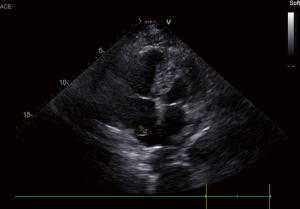

At 2 days after treatment, transthoracic echocardiogram demonstrated that the pulmonary artery pressure had decreased to 60 mmHg and there was no right atrial mass, thus the ECMO was weaned off (Figure 4). Considering the risk of the right lower extremity deep venous thrombosis leading to the PE again, a vena cava filter was implanted. The patient was discharged from the hospital in good condition, receiving warfarin anticoagulation therapy for 5 days following the vena cava filter (Figure 1). After another 25 days, the vena cava filter was removed and the patient continued to receive the warfarin with the dose of 3.0 mg per day to maintain the international normalized ratio (INR) between 2.0 and 3.0. And the course of treatment should be at least of 6 months (Figures 1,4,5).